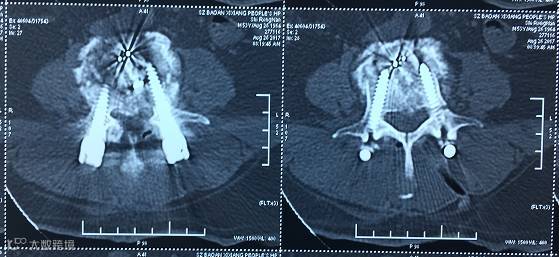

【术前CT】

【术后CT】